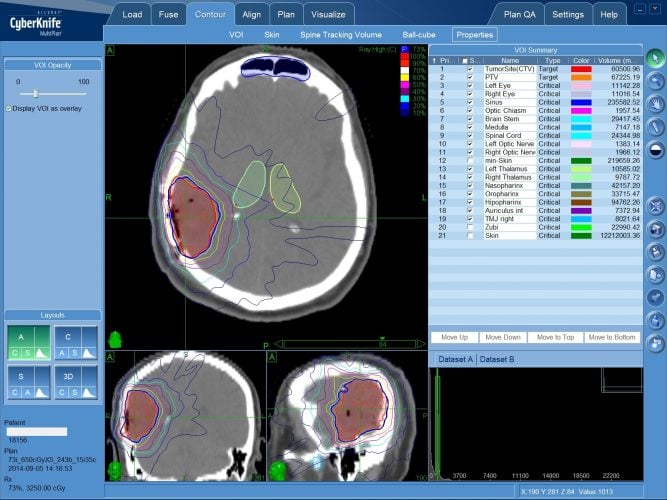

3. Променева терапія

Інша зброя арсеналу — променева гармата. Госпітальний апарат опромінює уражену зону. Пацієнт відчуває, наче його нейрони прожарюють в мікрохвильовці.